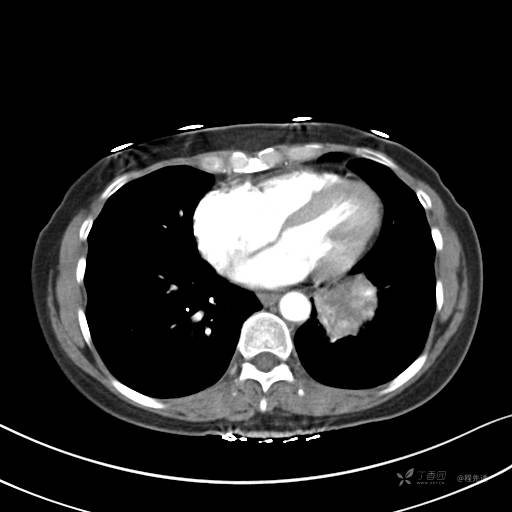

CT平扫

纵隔窗

病灶平扫CT值约31HU